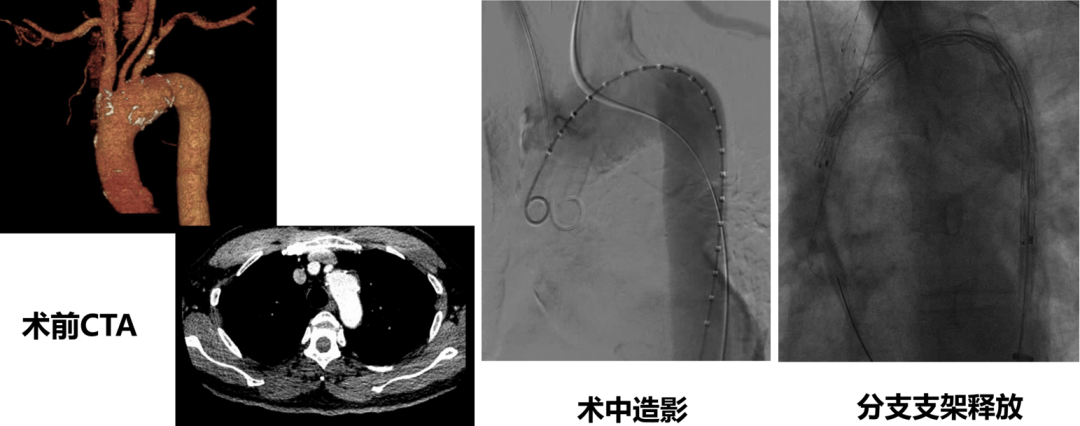

★ Case6:男,55岁, 胸痛4天入院。诊断:A型主动脉夹层

3D打印模型

分支前后体外预开窗

术毕造影

术后CTA